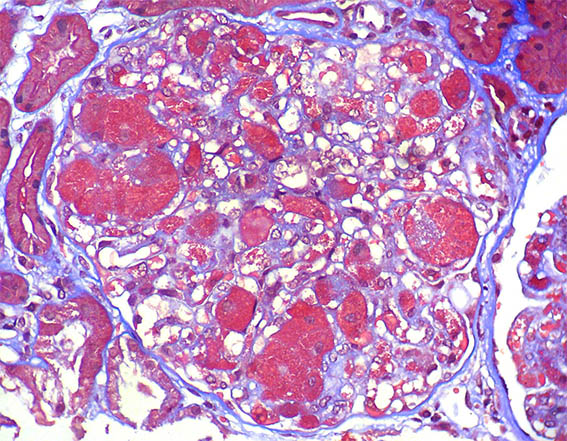

Se hace biopsia renal, observe las imágenes.

Figura 4. Tricrómico de Masson, X400.